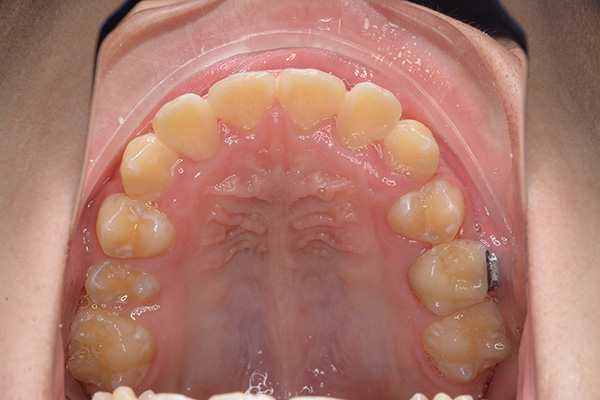

| 口腔内所見 | over jet 5.5mm,over bite 5.0mm,大臼歯関係はⅠ級 、Hellmanのdental ageはⅢBであり上突歯列を呈していた。 |

| パノラマ所見 | 上顎左右側犬歯は近心傾斜し側切歯歯根に重なるように認められた。 |